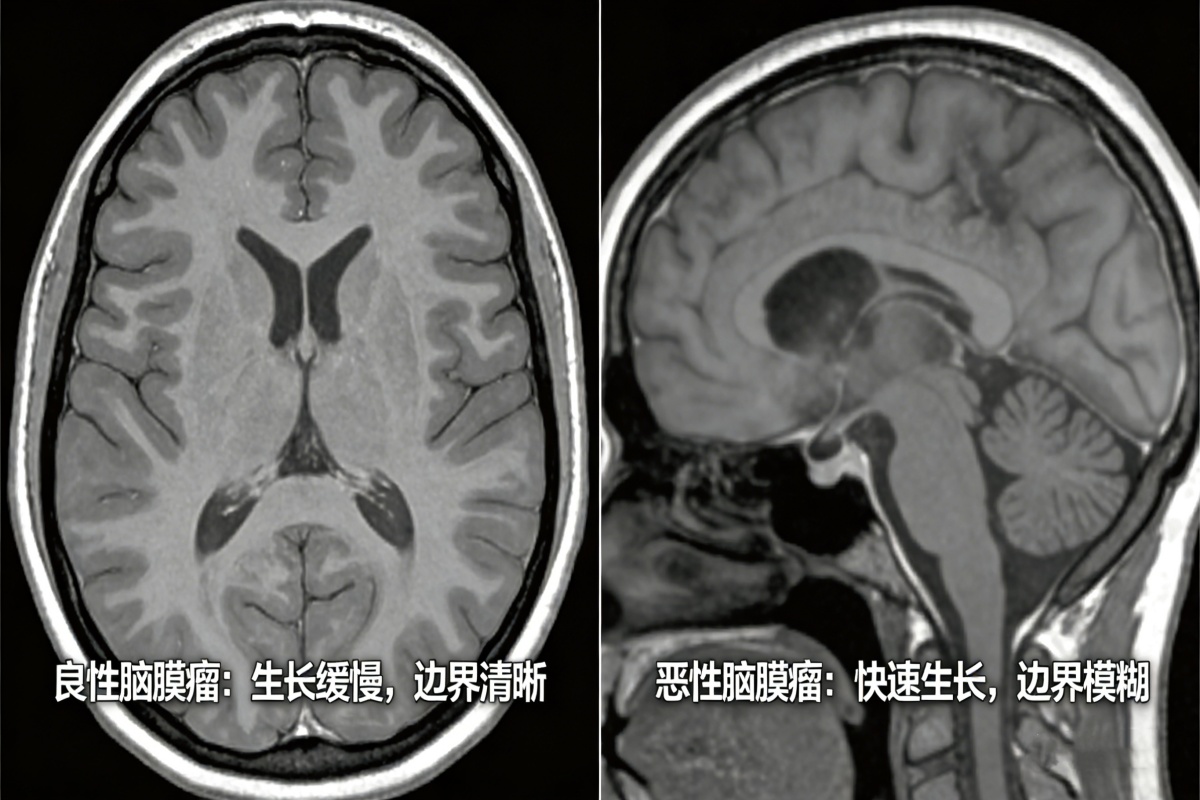

划重点:良性脑膜瘤vs恶性脑膜瘤,3个区别一眼分清

很多人分不清良恶性,其实看这3点就够了,不用记复杂的医学术语,普通人也能快速判断(最终确诊还是要靠医生的病理检查,这只是初步参考)。

1. 生长速度:良性“慢吞吞”,恶性“急冲冲”

良性脑膜瘤的生长速度非常慢,可能几年甚至十几年才会长大一点点,有的患者终身携带,肿瘤也不会有明显变化,对大脑的压迫很缓慢,早期基本没有症状。

而恶性脑膜瘤恰恰相反,生长速度极快,可能几个月就会明显增大,快速压迫脑组织、神经,导致头痛、头晕、视力模糊等症状突然加重,甚至出现肢体无力、癫痫等问题。

2. 侵袭性:良性“守规矩”,恶性“乱扩散”

良性脑膜瘤就像一个“懂事的肿块”,有自己清晰的边界,不会侵犯周围的脑组织、神经,也不会扩散到身体其他部位,只要通过手术完整切除,基本就能根治,复发率非常低(不足5%)。

恶性脑膜瘤则很“霸道”,没有清晰的边界,会像“树根”一样侵入周围的大脑组织、血管和神经,很难通过手术完全切除,而且容易复发,甚至可能扩散到脊髓等其他部位,治疗难度会大很多。